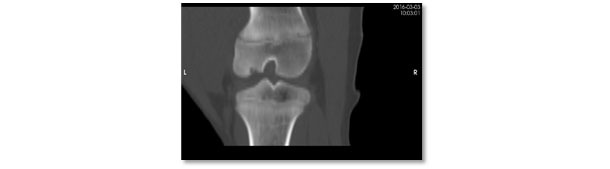

Visão de tomografia computadorizada da mesma lesão. Lesão grave de osteocondrose com ausência de ossificação na região subarticular do côndilo lateral do fêmur.